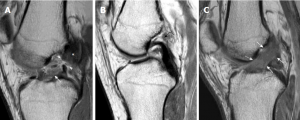

A:前交叉韧带撕裂的典型外观,前交叉韧带的纤维不连续(箭头)。股骨侧(星号)和胫骨侧(白色箭头)残端松弛、增厚、信号增强;

B:慢性前交叉韧带撕裂,正常前交叉韧带纤维缺失,纤维完全吸收。(弯曲的黑色箭头);

C:急性撕裂,以ACL纤维增厚和水肿性改变为特征,显示信号强度增加(白色箭头)。纤维仍保持连续性,提示前交叉韧带部分撕裂。